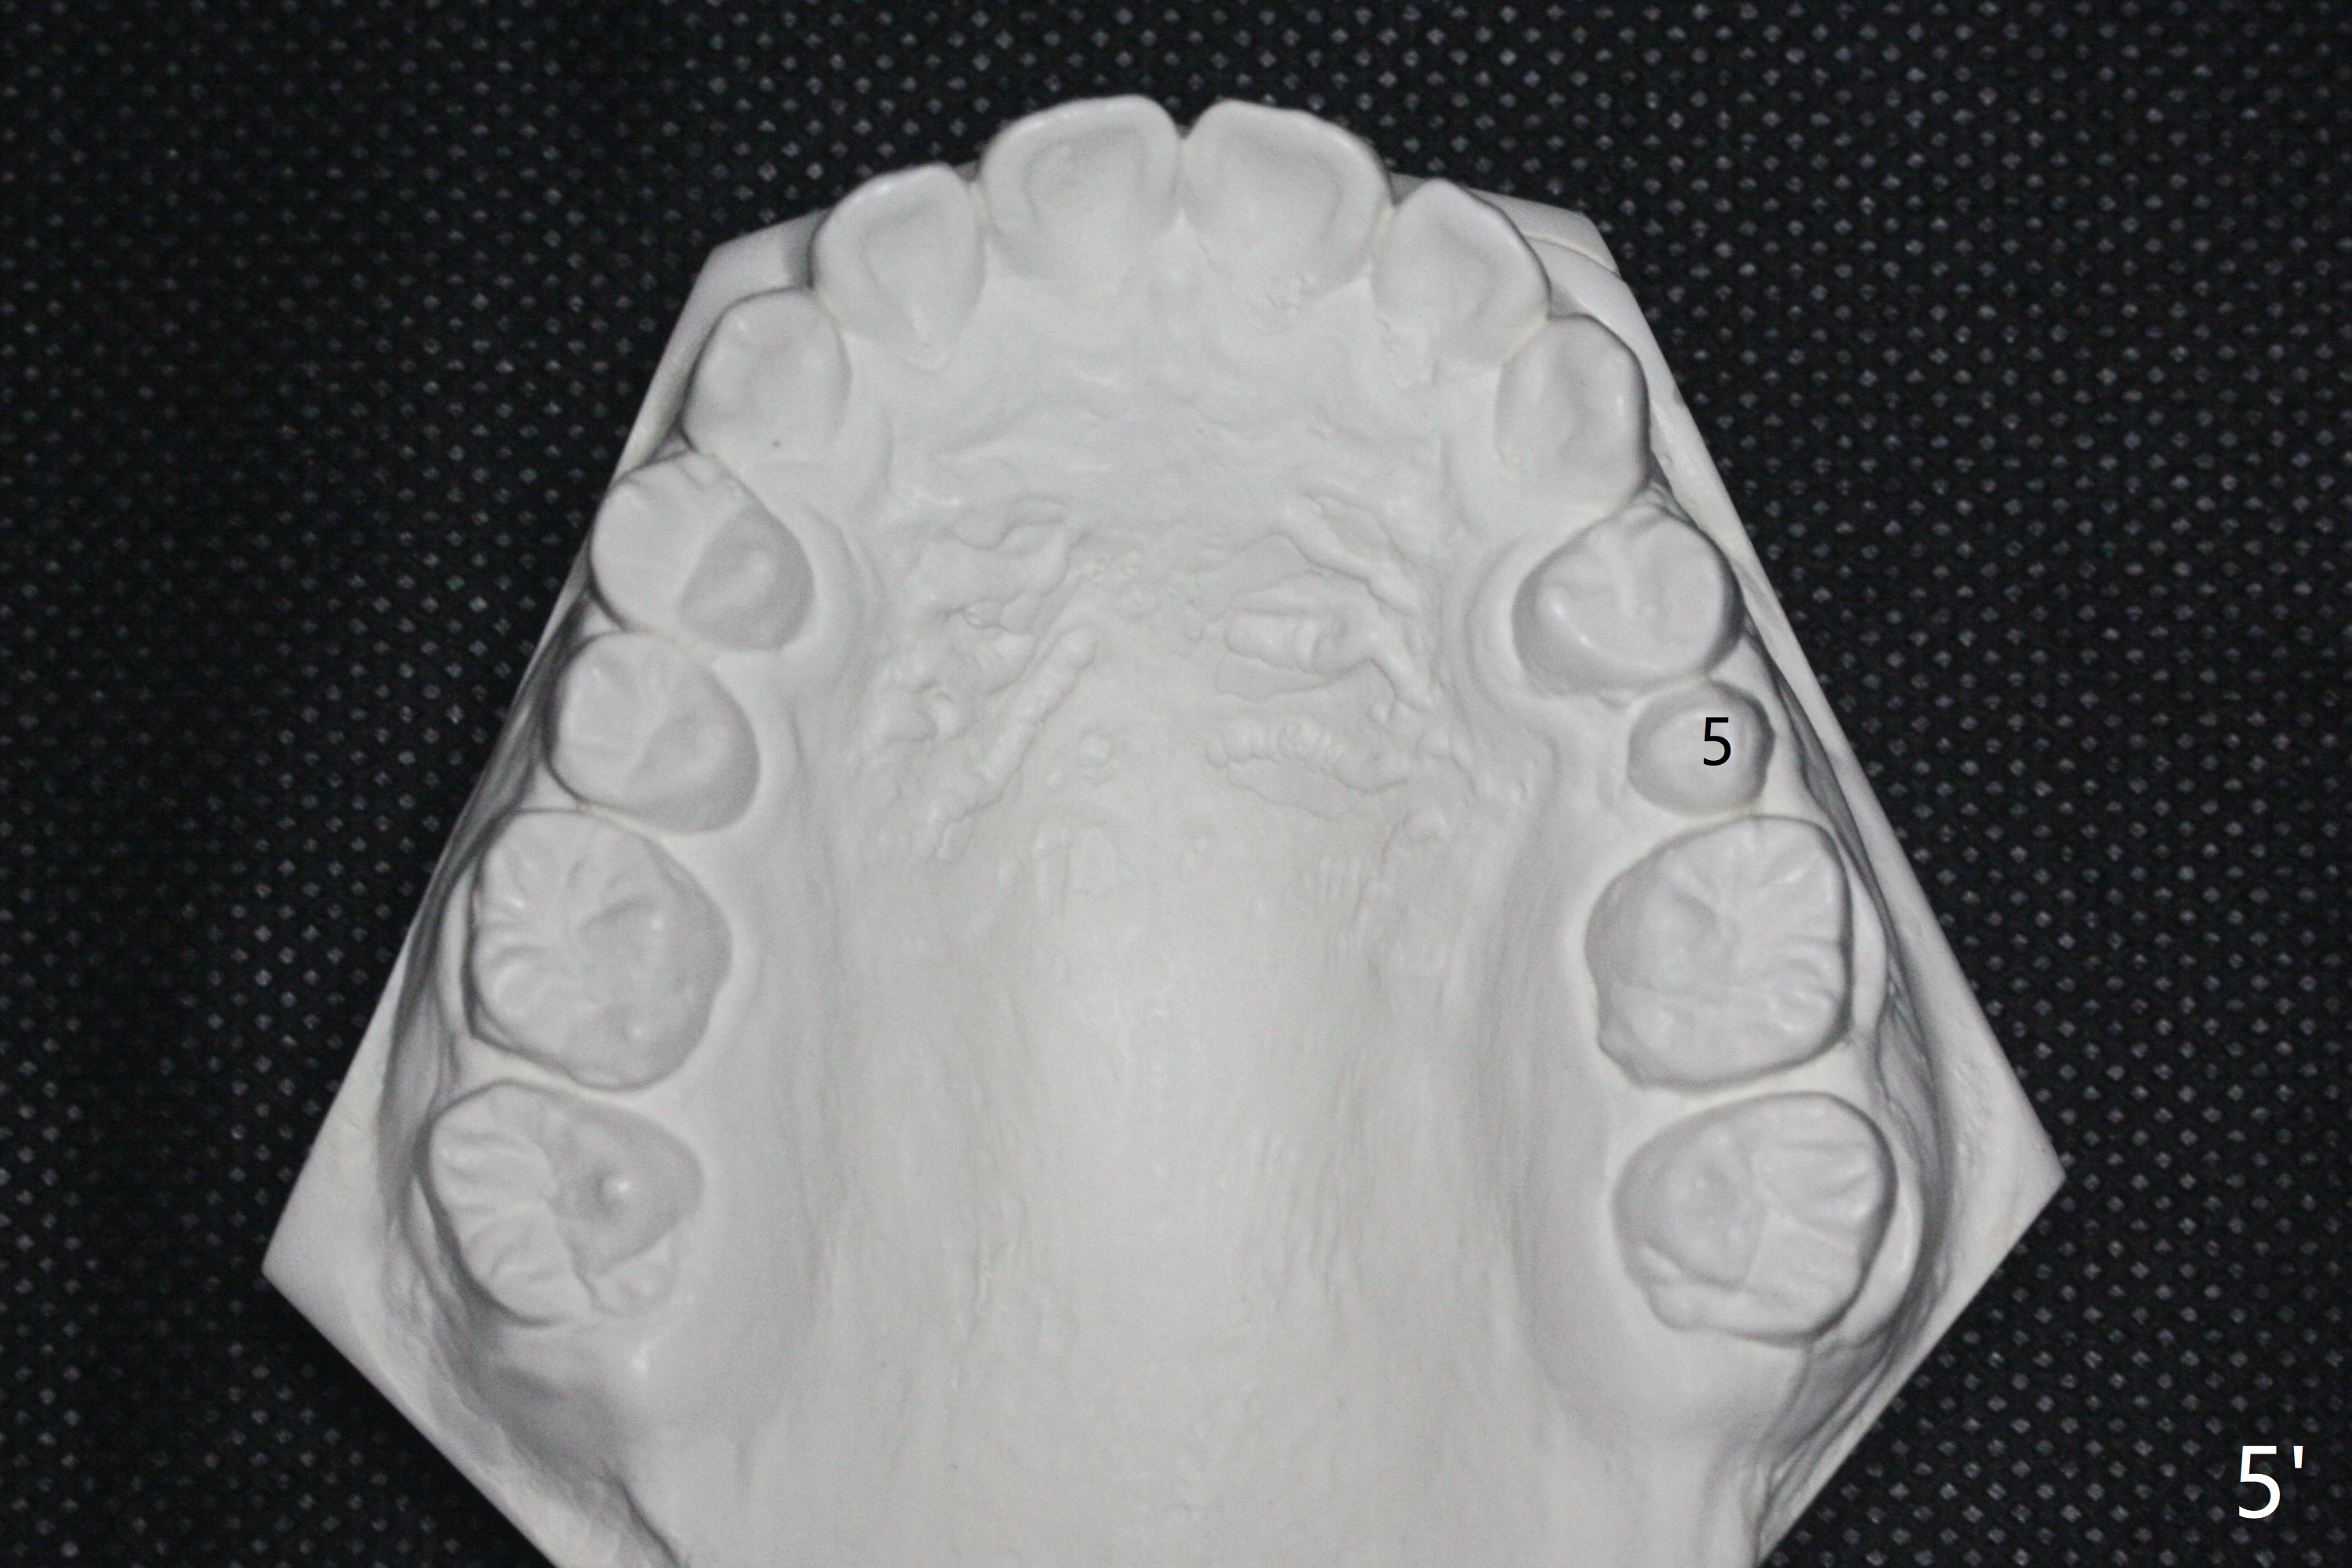

One-year-8-month orthodontic treatment reduces anterior overjet (Fig.1 (double arrows),1', with facial profile improvement), corrects right 1st molar cross bite (Fig.2,2') and dental midlines (Fig.3,3'), closes the diastema between UL3 and 4, extrudes UL5 (Fig.4,5,4',5'), and increases space for future implant at LL4 (Fig.6,6'). In fact large arches with distemata make the treatment possible! Extrusion of UL5 leads to root development (Fig.7, 7' (R)). The increased space at LL4 (Fig.7' *) appears insufficient for an implant.